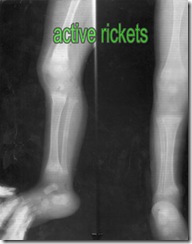

pediatrics x-ray about rickets with diagnosis

This is pediatrics x-ray about rickets with diagnosis